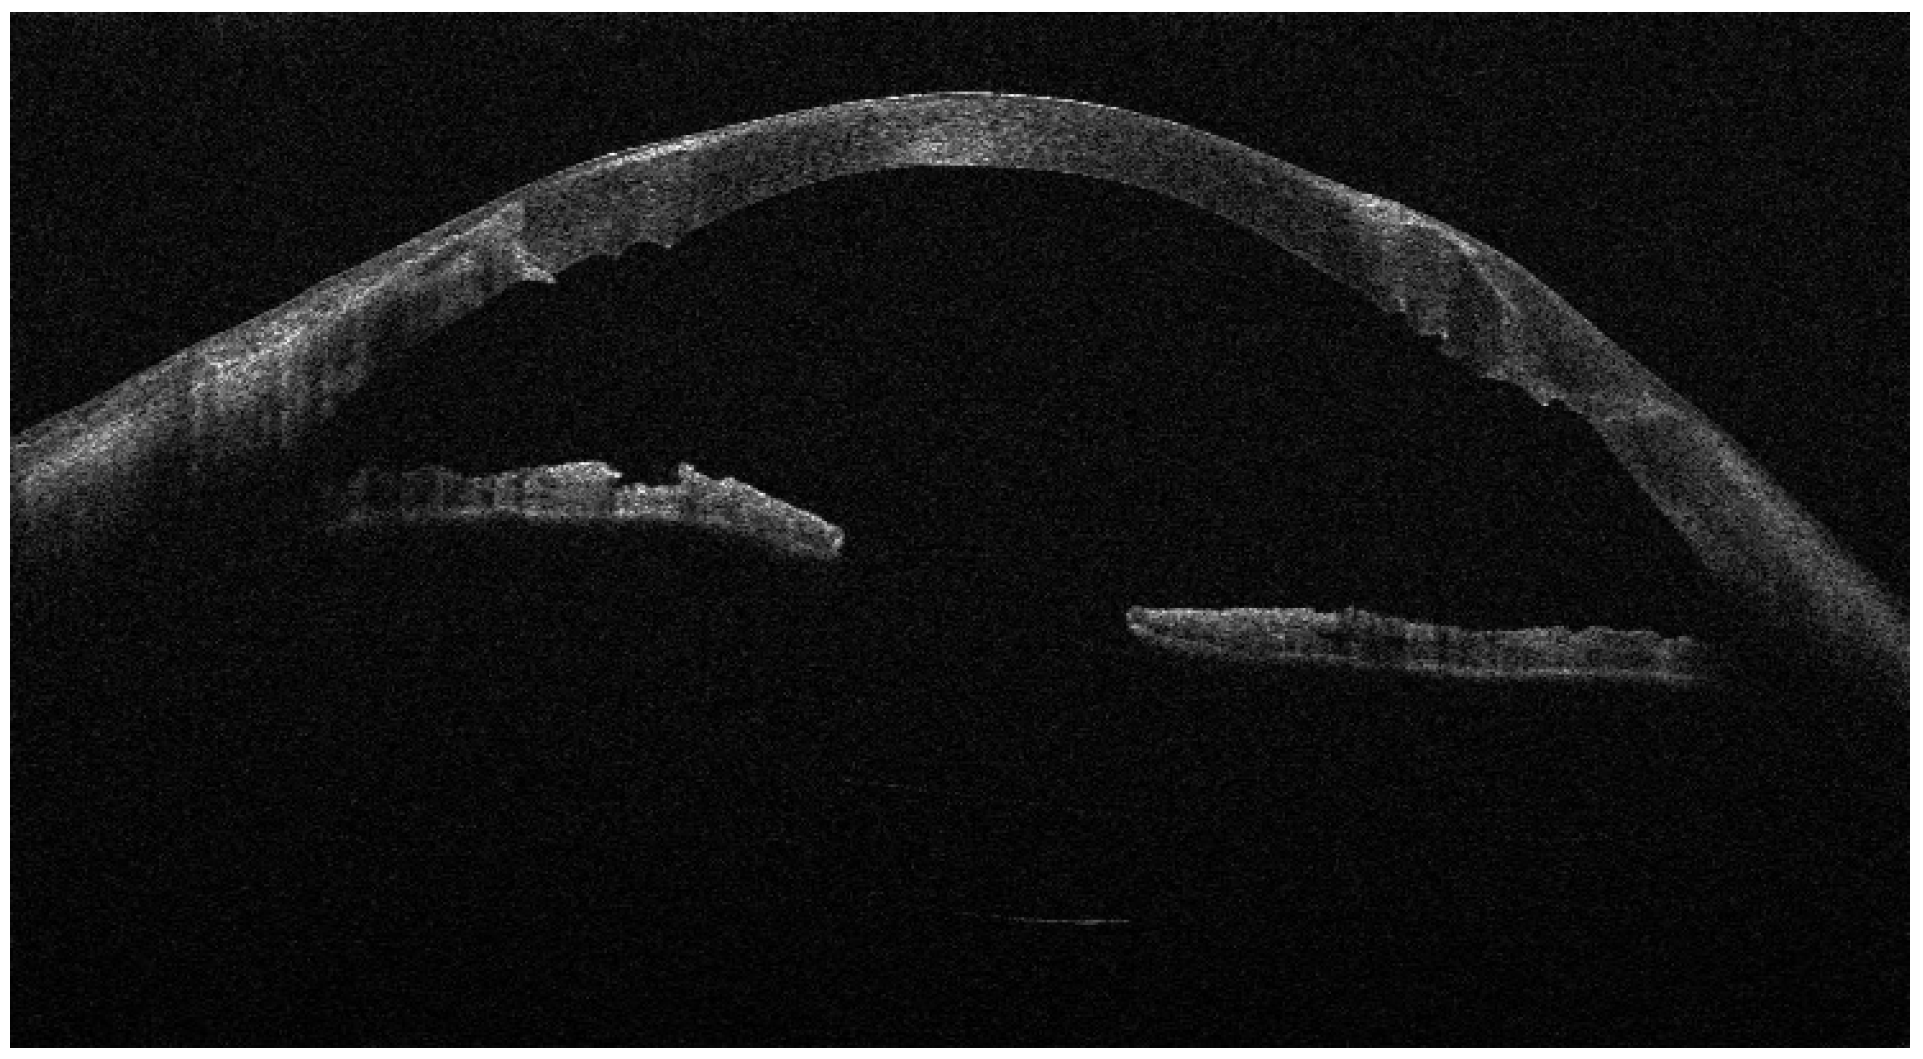

Figure 2. AS-OCT showing the lamellar patch graft centered on the perforation site and covered by the amniotic membrane; the AM appears as a thin hyperreflective layer over the graft surface.

From September 2023 to December 2023, the patient was managed with intensive topical antimicrobial therapy for the corneal abscess, together with aggressive ocular surface support for severe oGVHD-related epithelial instability (preservative-free lubricants, protective bandage contact lens/scleral protection when tolerated, and adjunctive therapies according to the ocular surface status). Despite these measures, progressive stromal melting occurred, culminating in a 4 mm full-thickness perforation in December 2023, prompting urgent tectonic surgery. Standardized preoperative slit-lamp photographs immediately before the urgent repair were not consistently obtainable due to the emergent nature of the procedure and the compromised ocular surface; therefore, urgent repair was performed with a lamellar corneal patch graft wrapped in cryopreserved amniotic membrane (Figure 1 and Figure 2). Cryopreserved human amniotic membrane (AM) was thawed according to the manufacturer’s instructions and rinsed with balanced saline solution. A single AM sheet was prepared to fully envelop the lamellar donor corneal patch. The donor lamellar graft was placed at the center of the AM sheet, which was then folded circumferentially to create a 360° envelope around the graft. The AM was oriented with the stromal side facing the donor corneal tissue and recipient bed, and the basement membrane/epithelial side facing outward, toward the tear film. The AM-wrapped graft was positioned over the corneal perforation and secured with interrupted 10-0 nylon sutures, ensuring complete coverage of the graft–host junction by the AM.